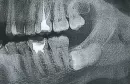

Недавно делал снимок (впервые за 36 лет). Оказалось, что обе нижние восьмерки лежат. Пока раздумываю, стоит ли их удалять или уже поздно. Однако насторожило то, что на снимке левой восьмерки не различимы корни, вместо них некое белое образование, едва ли не больше самой коронки.

Является ли это показанием к удалению? Не усложнит ли это и без того непростой процесс?

Это искажение снимка.

Удаляйте спокойно, ничего в этом страшного нет.